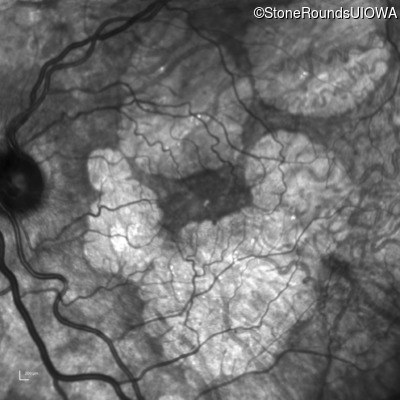

Age at visit: 51 years

This 51 year old woman first experienced some abnormality in her distance vision when she was 27 years old. She feels that her vision has been stable since that time.

Diagnosis & molecular findings

AR Stargardt Disease ABCA4 Gly1507Arg GGG>AGG IVS42+1 G>A AR